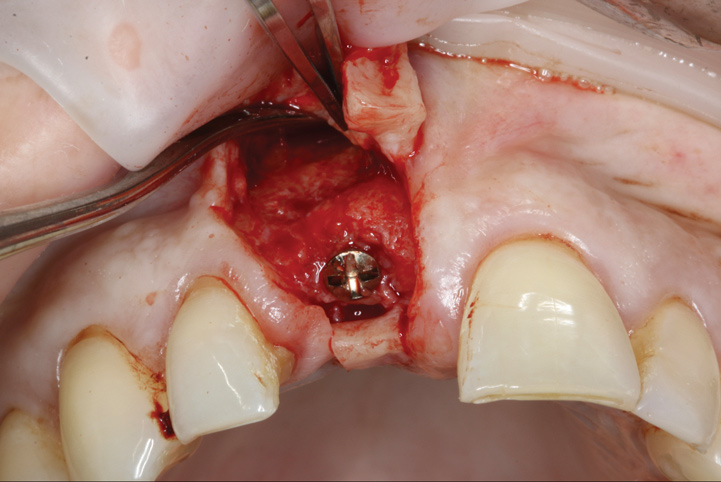

Prior to the initiation of the surgery, the surgical guide was tried in to confirm proper seating and stability (Figure 15). A flapless approach was not considered because the need for further bone grafting at the time of implant placement had been anticipated through the digital planning. A slightly palatal crestal incision was made, followed by two vertical incisions on the mesial and distal aspects of the edentulous site in order to preserve the papilla and avoid additional esthetic compromise to the anterior sextant. Next, a full-thickness flap was elevated to facilitate removal of the tenting screw and permit visualization of the buccal plate (Figure 16). A standard guided protocol was followed to place the implant, and its final position mirrored that of the digital plan. As predicted, the prosthetically driven implant position resulted in an insufficient buccal plate (Figure 17); therefore, additional guided bone regeneration was performed to reinforce the area and prevent future breakdown (Figure 18 and Figure 19). Making periosteal incisions could have compromised the blood supply to the flap, so instead, it was stretched in order to achieve tension free coronal advancement.31The flap was secured utilizing horizontal mattress sutures with additional supportive interrupted sutures to ensure primary closure (Figure 20). An immediate postoperative periapical radiograph (Figure 21) and CBCT scan (Figure 22) were taken, demonstrating a final implant position centered with the planned location of the gingival zenith.

(16.) Full-thickness flap elevation to expose the tenting screw and gain access for anticipated additional bone grafting following implant placement.

Figure 16

(17.) Implant placed 1-mm distal to the midline of the edentulous space, corresponding with the planned location of the gingival zenith. Note the lack of sufficient bone buccal to the implant that necessitated further grafting.

Figure 17